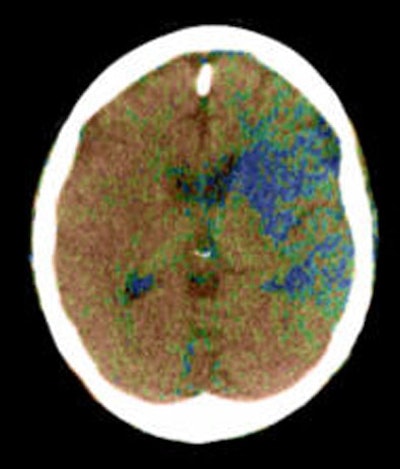

| Top to bottom: Perfusion CT images overlaid on CT source images of a 73-year-old male patient. The patient was scanned 30 minutes after the sudden onset of right hemiparesis with an NIHSS of 20. Above, cerebral blood flow (CBF) map shows a blue-color area of low CBF (range: 0-12 mL/100g/min) in the basal ganglia on the left side, which corresponds to the irreversibly infarcted tissue. Note the peripheral area displayed as green, which corresponds to the penumbra region (range: 12-24 mL/100 g/min). In the image below, cerebral blood volume (CBV) map does not demonstrate a clear delineation of the infarcted region in comparison with the CBF map. In the bottom image, mean transit time (MTT) map shows a slightly larger abnormality than seen on the CBF map. Images courtesy of Dr. Sotirios Bisdas. |